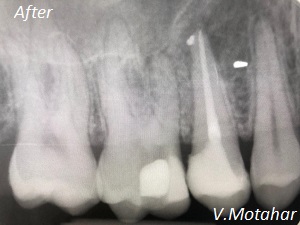

Root Canal treatment on Lower molar tooth immediate after the Root Filling!

before

after

Root canal treatment on three rooted tooth! which had 4 canals!